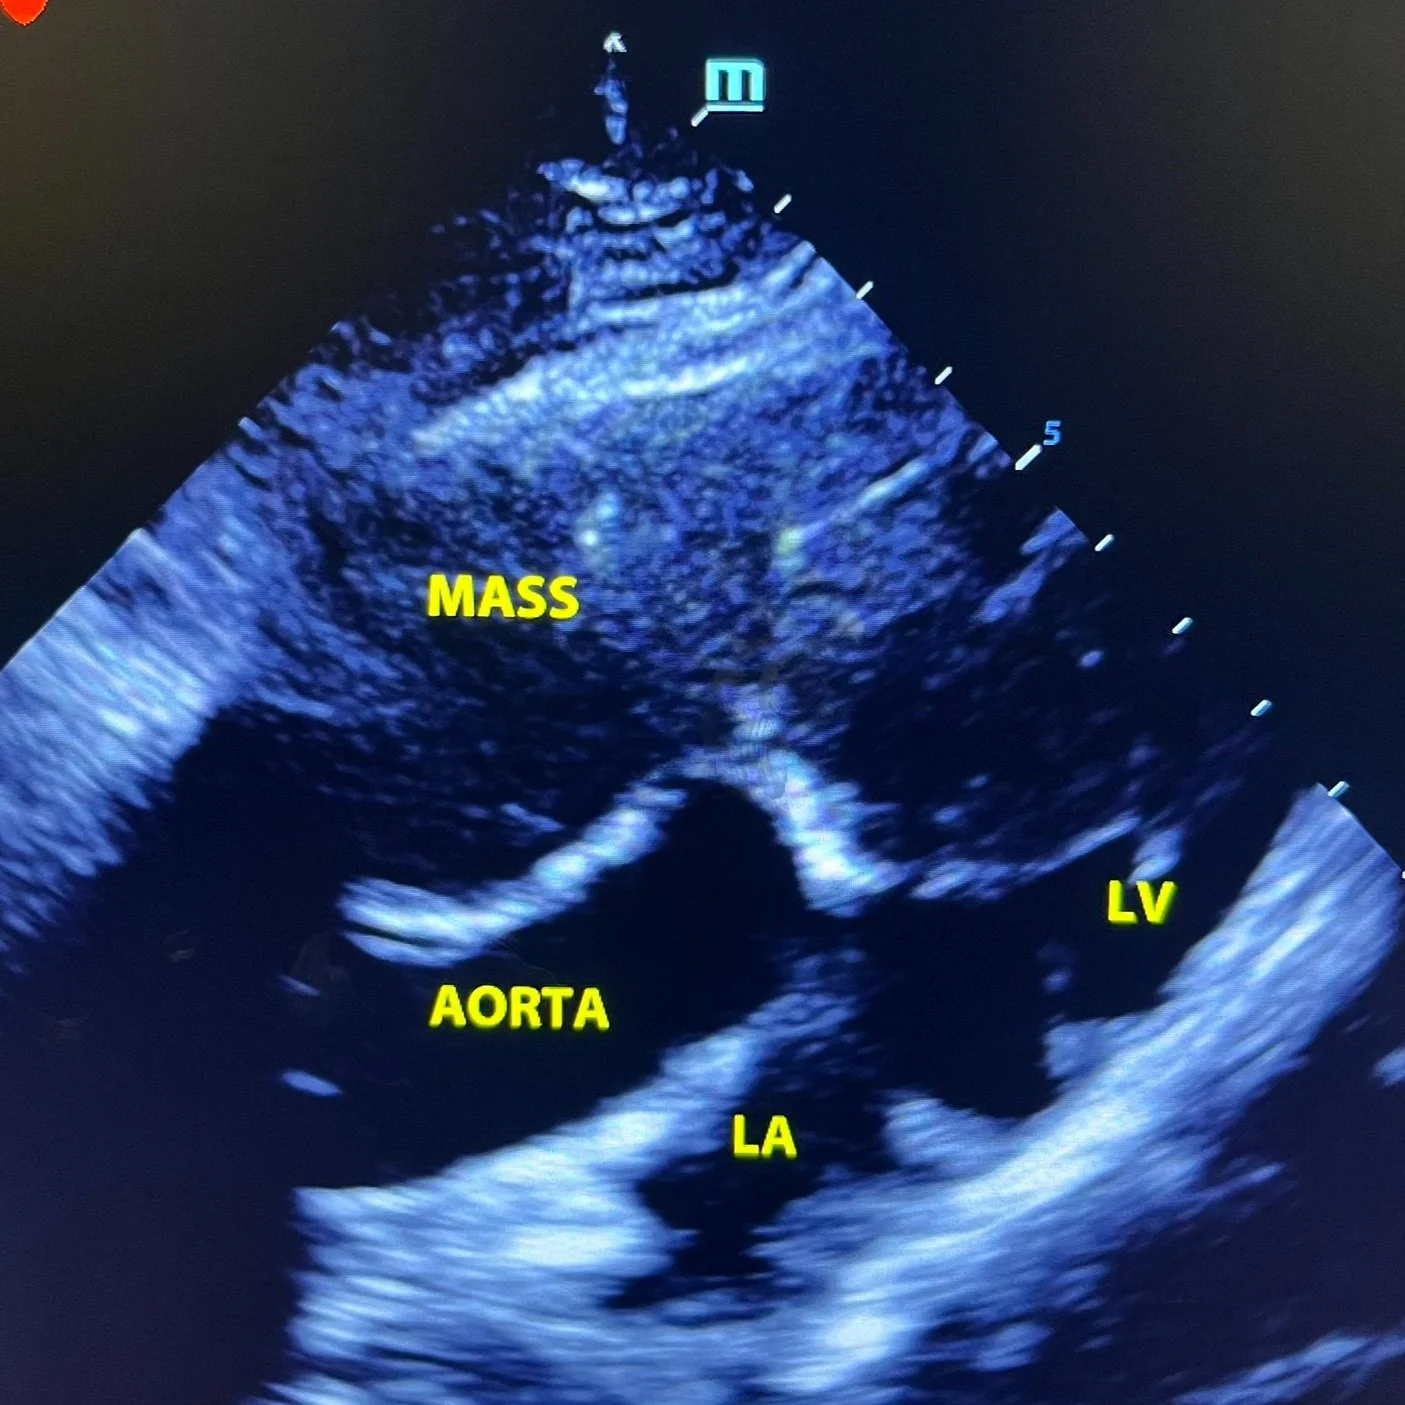

During a veterinary ultrasound, we use a small handheld probe that glides smoothly over your pet's fur and skin. The probe emits sound waves that bounce off internal organs, allowing us to create live, detailed images of your pet's internal structures on a monitor. This allows us to examine the abdomen, heart, or other areas with precision, capturing important information without causing any discomfort to your pet.